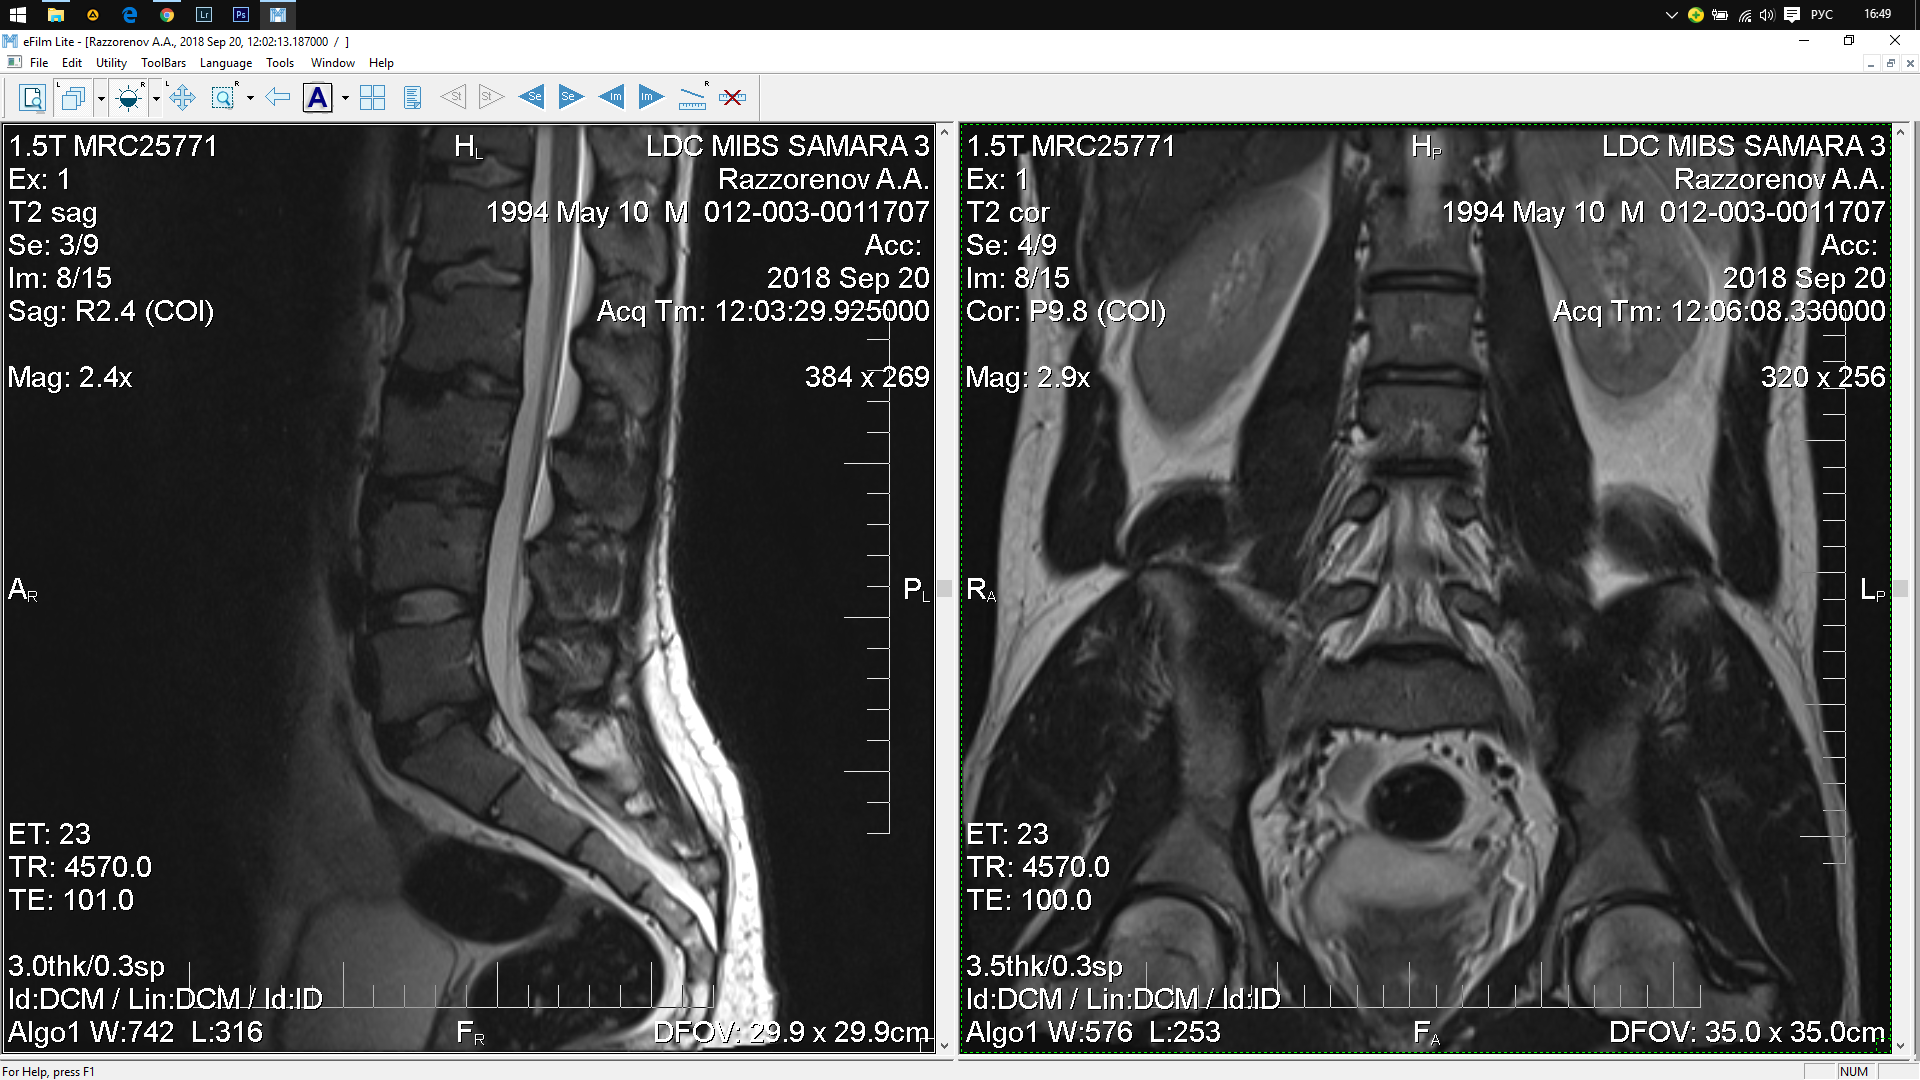

Тренировки с межпозвоночной грыжей.